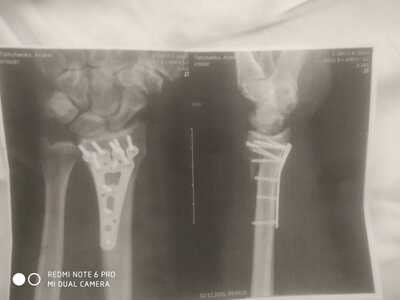

У меня ДТП. Я за рулём, на меня на встречку вылетел лоб в лоб. Очнулся в больнице. Левую ногу и левую руку собирали. Вот на руке шрам страшный. Из последствий нога короче на 3см. Спец обувь. А так, спустя 1,5 года всё отлично)))) но металл пока во мне. Не знаю, буду вынимать или нет. И так натерпелся операций, не хочу....

У меня оскольчатый фрагментарный перелом диафиза бедра со смещением отломков. Шрамов теперь ояебу. Помимо шрама на ноге, шрам от полостной операции на животе, страшенные шрамы на коленях, на плече, на боках. Так что, у тебя ещё не так всё плохо:) мне всё тело забивать тату придётся